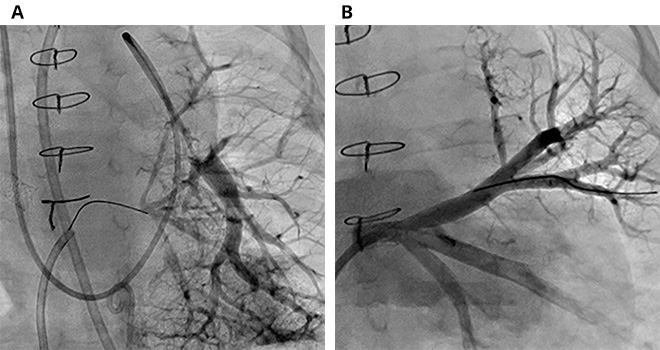

A) Left pulmonary artery wedge angiogram demonstrates loss of the entire left pulmonary vein network, while a wire is advanced from the left atrium in an effort to reopen the pulmonary vein.

B) After successful opening and stenting of the vessel, and with advanced medical management, the left pulmonary veins are widely patent at follow-up one year later.